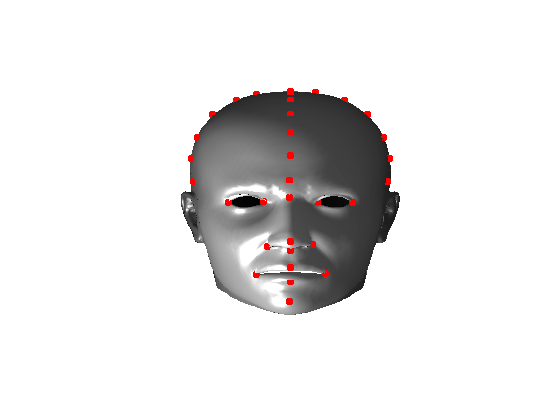

7 Extension to 3D full head modelling

Using the ECN pose normalisation technique described in previous sections, we have built a 3D statistical model of the full head, including face and cranium, using the same 100 scans of adult males as we used in the cranial profile model described earlier. We employed a variant of a template morphing technique called Optimal-Step Non-rigid Iterative Closest Points (OSNR ICP) [11]. However, its application to the full human head is more difficult than with face only, due to the lack of well-defined landmarks for initial alignment over the cranial area.

Pose is normalised using the ECN method, and relies on the symmetry plane, ellipse centre and nasion position, as shown in Fig. 25. We then find a set of pseudo-landmarks on the cranial surface by 3D ray projection over a predefined set of angles, as shown in Fig. 26. The same processes are applied to a template mesh of the human head, so that it has the same set of both face and cranium landmarks.

The template mesh is then warped in a global affine sense, as shown in Fig. 27 to minimise the least-squares error between the two sets of landmarks, when the head scan is fixed in its canonical poose. After this initial stage, landmarks and pseudo-landmarks are used in the same way as any other mesh vertex, as they are potentially noisy, as seen in earlier results analysis. This contrasts with Amberg et al’s [11] approach where the influence of landmarks is gradually faded out.